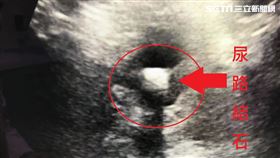

男每天尿30多次 尿路驚卡2顆結石

澎湖一名69歲退休公務人員的李阿伯,前陣子每天排尿次...